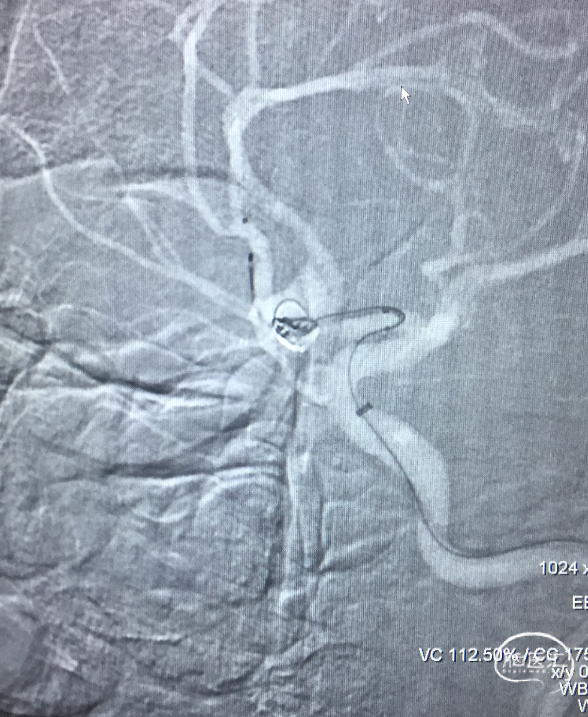

栓塞后即刻影像

工作角度造影显示动脉瘤栓塞致密,LACA A1、ACoA、双A2显影良好,左A2似有血栓(左图)。直头SL-10退至LACA A1末端,推注替罗非班1ml(右图)。

用药后再造影

再造影,发现RACA A2显影差,局部推注替洛非班无效,考虑前交通动脉血流受限,决定支架内球囊扩张。